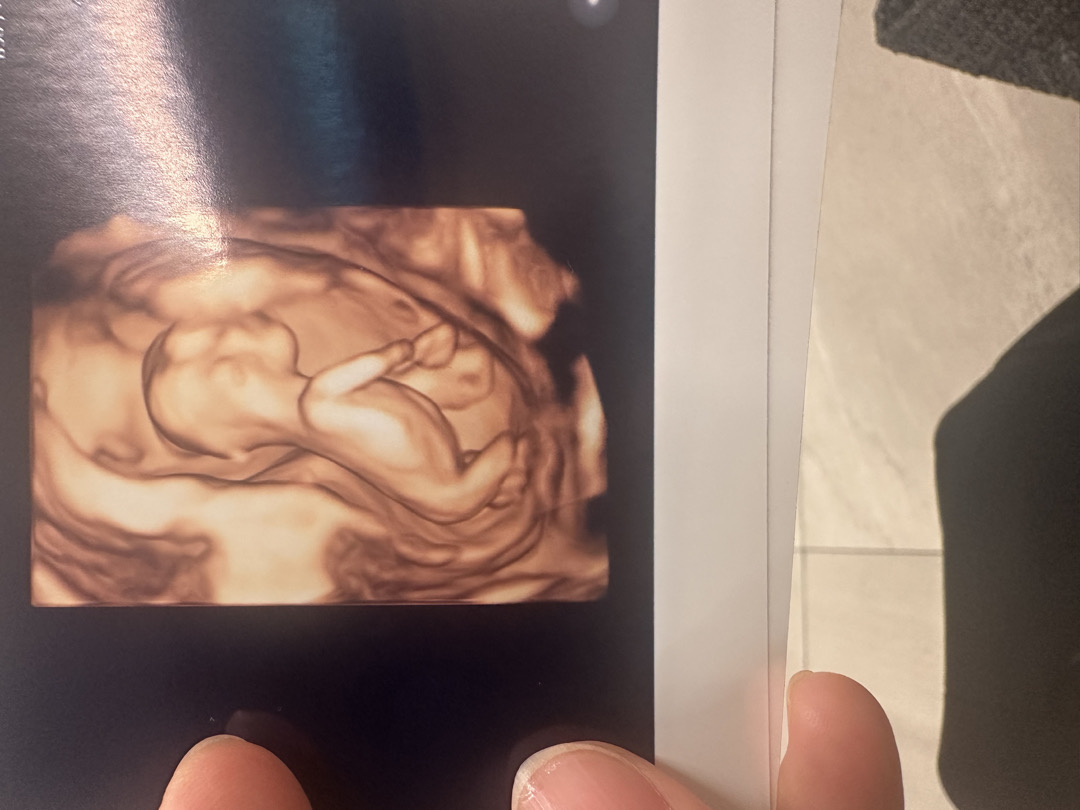

12주차 혹시 아들…?

아들인걸까요..? ㅎㅎ 목 투명대 검사하러 왔는데 뭔가 계속 보이는건 저의 매직아이 인걸까요?ㅎㅎㅎㅎㅎ;;;;

이건 정면 사진인데 뭐가 보이시는 맘들 계신가요~?ㅎㅎ

여기 추가 사진도 올려드려요~ 고수님들 봐주세요 ㅎㅎ

아들 같아 보이죠~? 밑에 사진두 봐주세요:-) ㅎㅎ

아들이 맞았어요!!!ㅎㅎ 역쉬👍🏻👍🏻👍🏻❤️